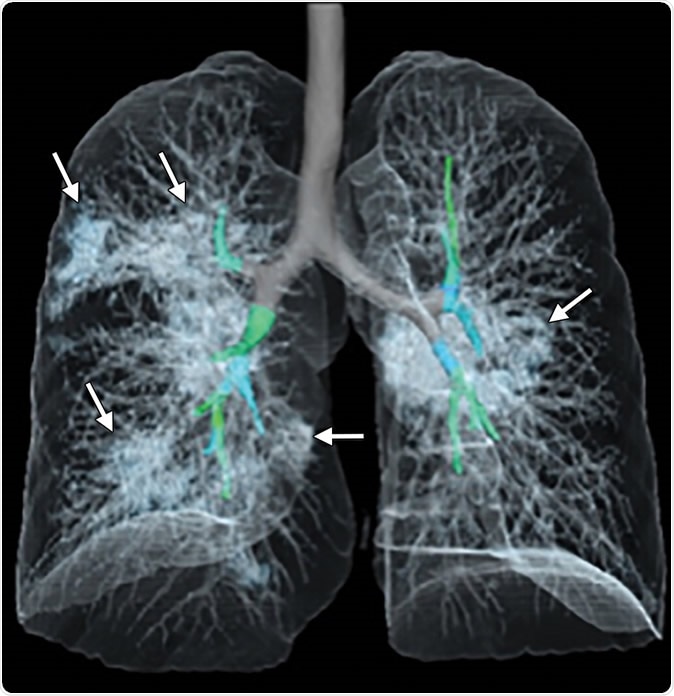

Images in a 41-year-old woman who presented with fever and positive polymerase chain reaction assay for the 2019 novel coronavirus (2019-nCoV). (a) Three representative axial thin-section chest CT images show multifocal ground glass opacities without consolidation. (b) Three-dimensional volume-rendered reconstruction shows the distribution of the ground-glass opacities (arrows). See also three-dimensional Movie (online).

The study examines the chest X-rays, and CT scans from over 20 patients aged 10-74 years, with symptoms of COVID-19. The scans showed inflamed lungs with ground-glass opacities, which look like white lung patches. These opacities are due to the partial clogging of the lung alveoli with tenacious mucus. Autopsies of Chinese patients who died of the illness because of breathing difficulties show lungs with minimal capacity for air inhalation due to the mucus accumulation.

The RSNA study shows how fluid accumulation in the lungs slowly worsens as the illness progresses, but then drains away if recovery begins until the lung spaces are completely clear.